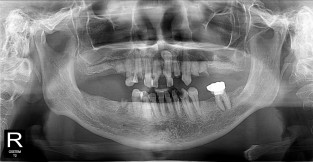

하악

치료기간 : 2021-11-30 ~ 2022-07-13

1. 상기 x-ray 이미지 모두 동일한 해당 의료기관에서 진료한 환자입니다.

2. 상기 x-ray 이미지 모두 동일 인물의 것입니다.

3. 치료 전 이미지는 2021-11-30에 촬영했으며, 치료 후 이미지는 2022-07-13에 촬영하였습니다.

4. 상기 x-ray 이미지 모두 동일 조건에서 환자분의 동의를 받아촬영되었습니다.

* 임플란트 시술은 환자분의 상태(고혈압, 당뇨 등)에 따라 부작용이 있을 수 있으니, 반드시 전문의와 상담이 필요합니다.

* 임플란트 수술 부작용

: 수술 후 출혈, 교합, 통증, 붓기, 염증 등의 문제점이 발생할 수 있습니다.)